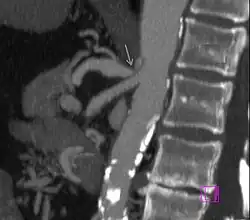

Further evaluation and confirmation can be obtained via angiography to investigate the anatomy of the celiac artery.[5] Historically, conventional angiography was used, although this has been largely replaced by less invasive techniques such as computed tomography (CT) and magnetic resonance (MR) angiography.[2][5] Because it provides better visualization of intra-abdominal structures, CT angiography is preferred to MR angiography in this setting.[5] The findings of focal narrowing of the proximal celiac artery with poststenotic dilatation, indentation on the superior aspect of the celiac artery, and a hook-shaped contour of the celiac artery support a diagnosis of MALS.[2] These imaging features are exaggerated on expiration, even in normal asymptomatic individuals without the syndrome.[2]

Proximal celiac artery stenosis with poststenotic dilatation can be seen in other conditions affecting the celiac artery.[2] The hook-shaped contour of the celiac artery is characteristic of the anatomy in MALS and helps distinguish it from other causes of celiac artery stenosis such as atherosclerosis.[2] This hooked contour is not entirely specific for MALS however, given that 10–24% of normal asymptomatic individuals have this anatomy.[2]